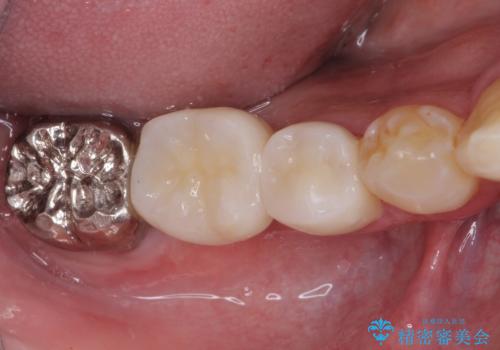

折れてしまった奥歯 インプラントによる補綴治療

診査の結果、5本の奥歯を抜歯してインプラントによる補綴治療が必要と診断されました。

左上に仮歯が装着されたからは咬み合わせが安定し、スムーズに治療を進めることができました。